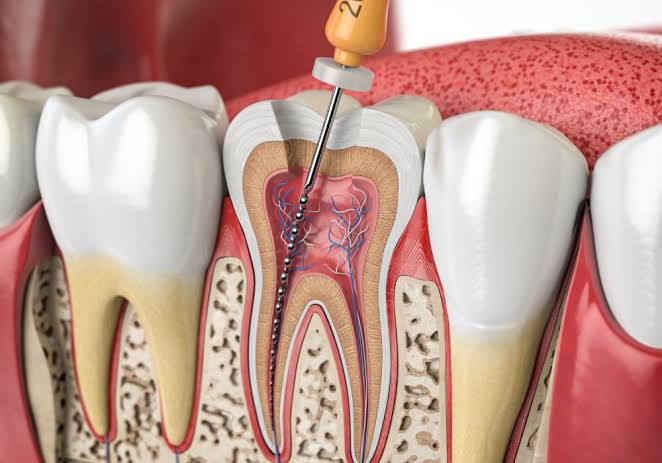

Comprehensive Dental Care

From cleanings and fillings to root canal therapy, tooth extractions, we provide expert care for every aspect of your oral health. Each procedure is performed with precision,